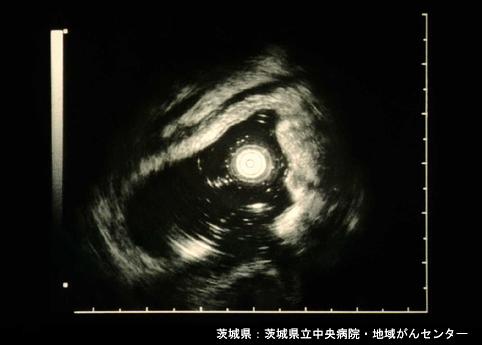

생체검사로 확인된 직장의 자궁내막증(---다지점 합동 소화관 텔레이미지 컨퍼런스 증례---증례제시:이바라키현, 이바라키현립 중앙병원・지역암센터 Dr.이타바시)

종양양 병변/자궁내막증

대장/직장

초음파

40이상